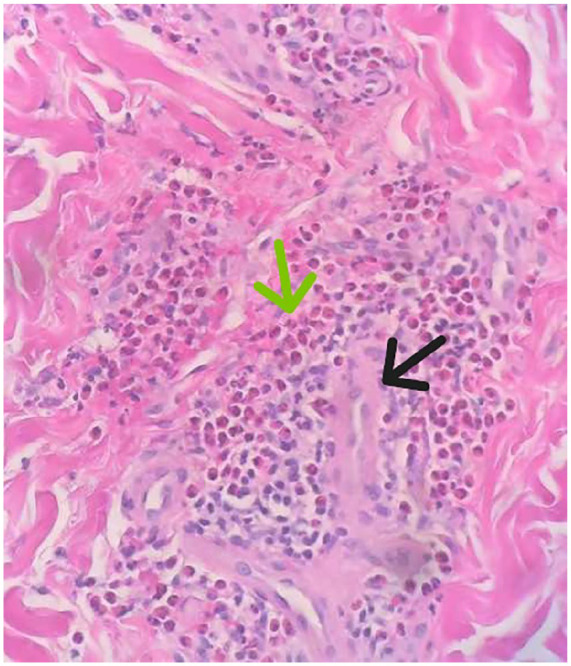

继发性嗜酸性粒细胞增多症最近引起了人们的关注,因为它可能导致血管病变,包括动脉瘤。本病例报告深入探讨继发性嗜酸性粒细胞增多与脑动脉瘤之间的复杂关系,这一联系在医学文献中尚未得到充分探讨。该病例以一名31岁女性为中心,她在无并发症妊娠后出现腿部疼痛、紫癜性皮疹和胃肠道症状。皮肤活检显示血管周围和间质性皮炎伴明显嗜酸性浸润,病因不明。实验室检查显示免疫球蛋白E (IgE)水平显著升高,为8400 kU/L。她的病情升级为弥漫性蛛网膜下腔出血并发现左小脑上动脉瘤。这种不寻常的表现,结合区分继发性嗜酸性粒细胞与原发性嗜酸性粒细胞疾病的挑战,提出了嗜酸性粒细胞在动脉瘤形成中的病理生理机制和临床意义的问题。我们讨论了嗜酸性粒细胞和血管损伤之间的潜在联系,并强调需要进一步研究以了解这种联系。临床上,该病例强调了考虑不明原因嗜酸性粒细胞增多症患者血管并发症的重要性。分享这些病例有助于在未来类似的演讲中更有见地和细致入微的方法,指导诊断和治疗策略。

Secondary eosinophilia has recently gained attention as a potential contributor to vascular pathologies, including aneurysms. This case report delves into the intricate relationship between secondary eosinophilia and cerebral aneurysms, a connection yet to be fully explored in medical literature. The case centers on a 31-year-old female who presented with leg pain, a purpuric rash, and gastrointestinal symptoms following an uncomplicated pregnancy. The skin biopsy revealed perivascular and interstitial dermatitis with a significant eosinophilic infiltration of unclear etiology. Laboratory investigations showed a markedly elevated immunoglobulin E (IgE) level at 8400 kU/L. Her condition escalated to a diffuse subarachnoid hemorrhage and the discovery of a left superior cerebellar artery aneurysm. This unusual presentation, combined with the challenge of differentiating secondary eosinophilia from primary eosinophilic disorders, raises questions about the pathophysiological mechanisms and clinical implications of eosinophils in aneurysm formation. We discuss the potential link between eosinophils and vascular damage and emphasize the need for further research in understanding this association. Clinically, this case underscores the importance of considering vascular complications in patients with unexplained eosinophilia. Sharing such cases contributes to a more informed and nuanced approach to similar future presentations, guiding diagnostic and therapeutic strategies.